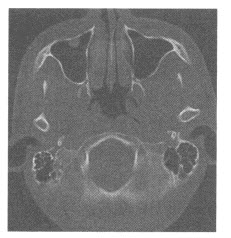

患者,女,16岁,偶感头痛,CT图像如下,可诊断为()

242、单项选择题

男孩,2岁,双眼疼痛1年,右侧眼球突出。CT平扫如图:

A.视网膜母细胞瘤

B.玻璃体萎缩

C.Coat病

D.视网膜发育不良

E.原始玻璃体增生症